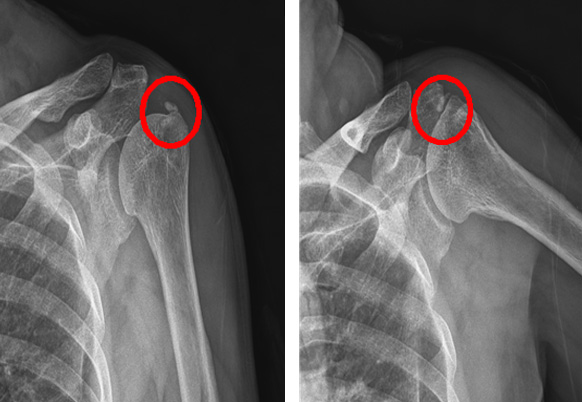

손목의 엄지손가락 부위 두 개의 힘줄을 둘러싼 건막(힘줄막)에 염증 생기는 질환으로 손목을 많이 사용하는 사람에게 흔히 나타나는 질환입니다. 출산 후 육아 중인 여성에게 흔히 볼 수 있으며 일상생활 중 키보드, 스마트폰 사용 등 힘줄을 반복적으로 무리하게 사용할 때 주로 발생하게 됩니다. 적절한 휴식, 약물치료, 물리치료(체외충격파) 등 보전적 치료로 회복이 가능합니다. 수개월간 통증이 지속된다면 주사 치료 또는 수술적 치료를 고려해 볼 필요가 있습니다.